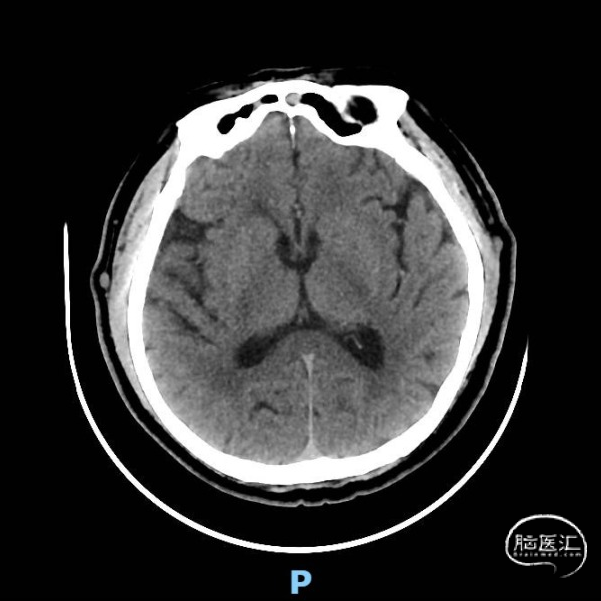

术前颅脑CT示:右侧脑室旁陈旧性腔梗。

随访:患者术后一般情况良好,自觉头晕、头昏症状明显缓解,血压、血糖控制良好,于术后第3天出院。